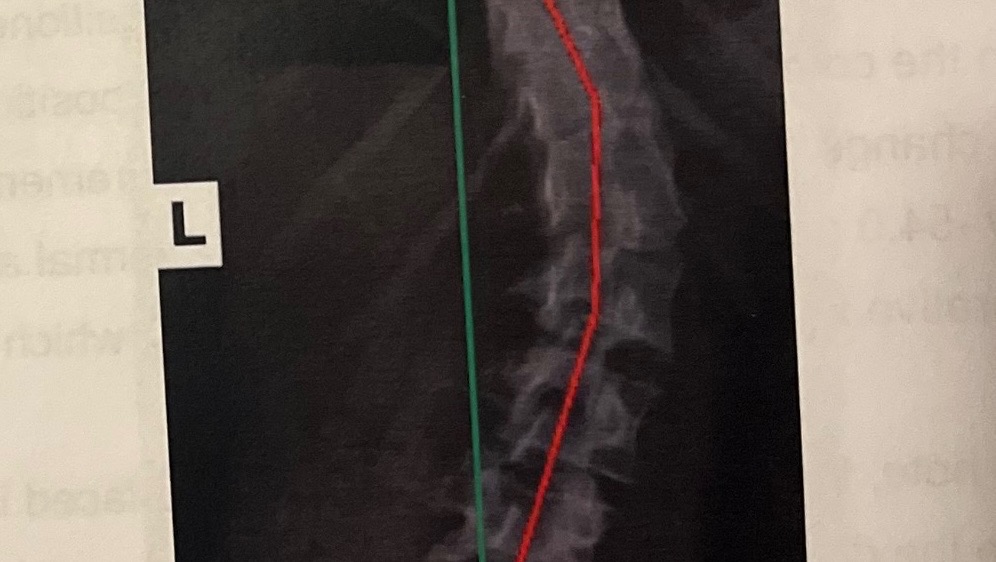

My daughter Kora has been living with severe daily pain for many years, unable to sleep through the night, and struggling with debilitating headaches. She is one of the strongest people I know. Despite facing daily pain and challenges from severe scoliosis, she’s never stopped trying to live her life to the fullest. She has two extreme spinal curves—one at her lower back at approximately 43 degrees and the upper at 35 degrees—that are causing significant health issues throughout her body. Without intervention, her condition will only continue to worsen, drastically affecting her quality of life.